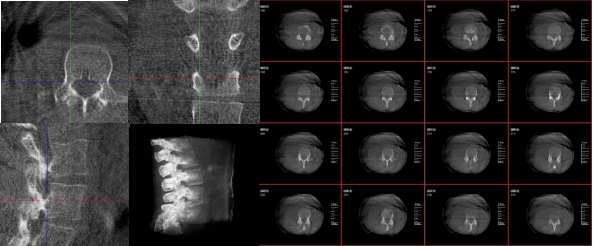

3.手術導航:在手術過程中,醫生可以通過三維重建技術實時觀察手術器械的位置,提高手術的精確性和安全性。例如在關節外科手術中,存在植入物的錯位在術中不易發現的情況,如果在術后CT中檢查出,就不可避免地需要翻修手術,這就會增加并發癥的概率以及感染風險。而通過術中三維影像設備PLX C7600的檢查,可以立即發現植入物的錯位,減少不必要的第二次手術。